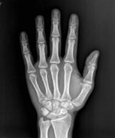

醫(yī)學(xué)影像學(xué)是一門理論性和實(shí)踐性均很強(qiáng)的應(yīng)用科學(xué),包括X線、超聲、MRI、核醫(yī)學(xué)及介入影像學(xué)等。主要用于臨床的各種疾病的診斷和治療,是影像醫(yī)學(xué)生必需掌握的一門課程,是成為一名合格影像醫(yī)生的必備技能。

學(xué)習(xí)醫(yī)學(xué)影像學(xué)是為了診療疾病有正確的保證。影像學(xué)診斷是對疾病進(jìn)行較精確定位、定性及定量今斷的學(xué)科,是臨床的常規(guī)檢查,已使過去不能診斷的疾病得到了早期適時正確的診斷和治療。影像技術(shù)的應(yīng)用在一定程度上決定了醫(yī)療水平的高低,關(guān)系到臨床各科室各種疾病的診斷,臨床醫(yī)學(xué)對影像診斷的依賴性越來越大。因此,掌握好各種影像檢查方法的適應(yīng)癥以及各種基本病變的表現(xiàn)是正確作出最恰當(dāng)診療的保證。